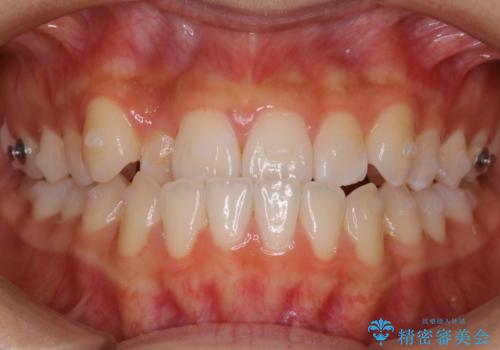

【非抜歯】受け口の改善 10代で始める本格的噛み合わせ治療

- 矯正装置

- マウスピース(インビザライン)

- 治療期間

- 1年6ヶ月

- 受け口の改善と前歯のガタつきの治療を主訴にご来院されました。

こちらの患者様の場合、上の前歯のガタつきが原因で口を閉じる際に上下の前歯の先端同士が先に当たってしまい、そこからさらに深く噛み込もうとすると下顎が前にずれていってしまうという、機能性の反対咬合であることが検査の結果わかりました。

そのため、まずは上顎の前歯のガタつきを改善していき、前歯が先に当たってしまうという症状を改善し噛み込む位置を後方の本来の位置に誘導する方法をとりました。